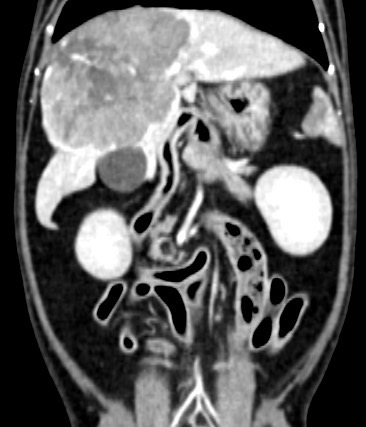

電腦斷層掃描

• 狗狗後腳癱瘓也有可能是血栓 不一定是骨骼神經肌肉問題喔

狗狗後腳癱瘓也有可能是血栓 不一定是骨骼神經肌肉問題喔